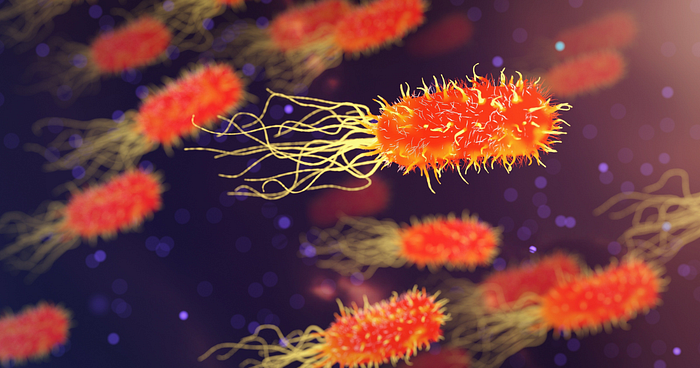

5. Antimicrobial Resistance (AMR)

Antimicrobial resistance (AMR) is an alarming global issue where bacteria, viruses, and fungi become resistant to the drugs designed to kill them. In 2024 and 2025, AMR is expected to become even more problematic due to the overuse of antibiotics in both healthcare and agriculture. This could lead to higher mortality rates from infections that were once easily treatable. Efforts to combat AMR will require global cooperation, stricter regulations, and responsible use of antibiotics.